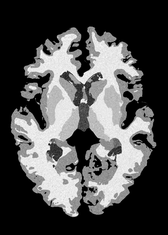

4.2 Registration to a 100 micron ex-vivo brain MRI volume

To showcase the efficacy of our method on real large scale images, we register a 250 in-vivo MRI image (Lüsebrink et al., 2017) to a 100 ex-vivo FLASH human brain volume (Edlow et al., 2019). This represents an inverse problem with more than 11.2B optimizable parameters (compared to 20M for clinical datasets), or 44.8GB of GPU memory. The entire problem does not fit on most GPUs, necessitating distributed multimodal registration. We optimize a composite transform - affine followed by a diffeomorphic mapping; details can be found in Section E.1. Multimodal deformable registration took 58 seconds on 8 NVIDIA A6000 GPUs, which is unprecedented at this resolution. Fig. 6 shows qualitative results, highlighting the ability to register highly detailed structures such as cerebellar white matter; these structures are not visible at macroscopic scales. The resultant advantages of performing registration at this scale can allow researchers to characterize the neuroanatomy at microscopic resolutions and allow morphometric analysis of cortical layers and subcortical nuclei among other structures.